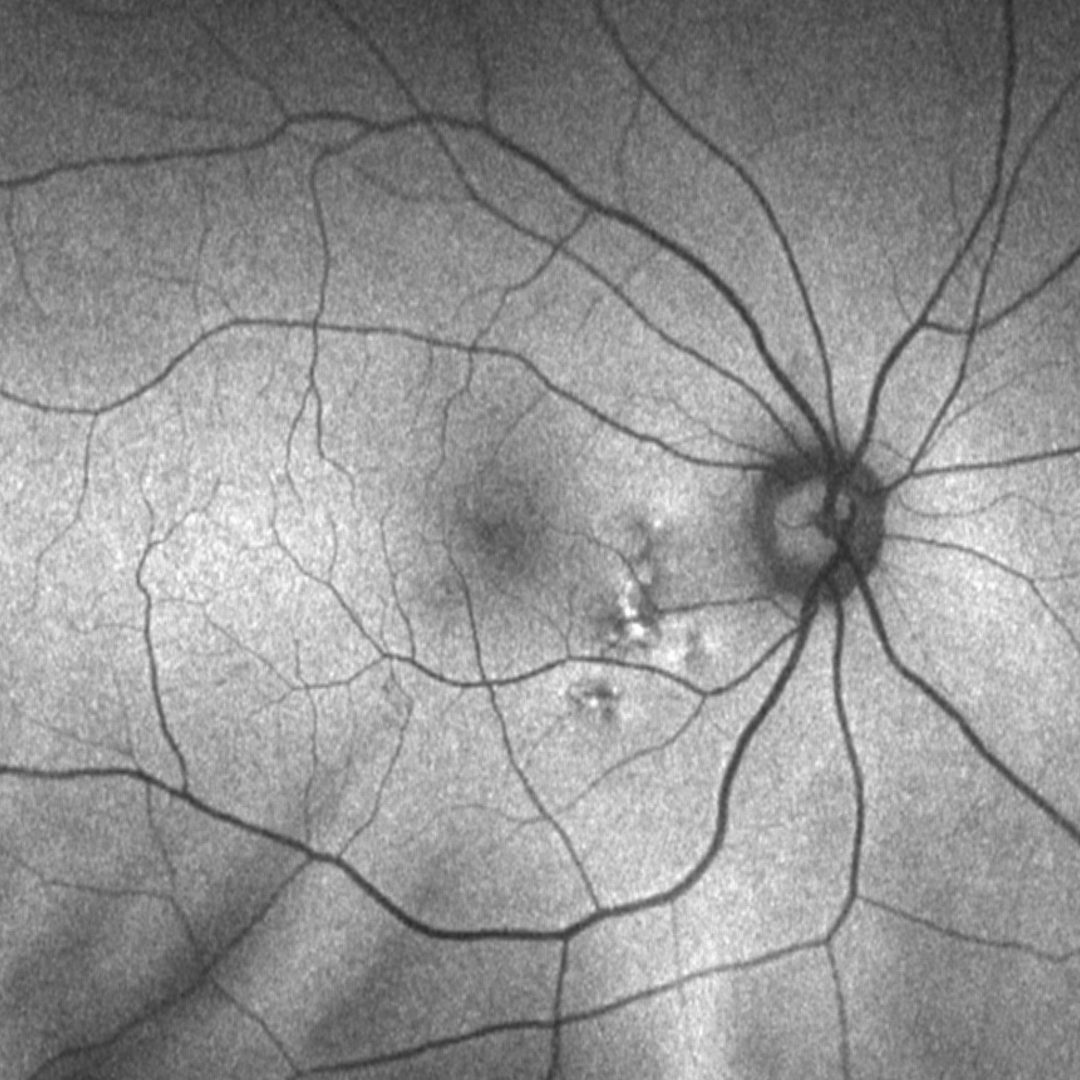

Fundus autofluorescence imaging can show a granular hypo-autoflurorescence or a mixed stippled hypo and/or hyper autofluorescence.

Fundus photograph and red-free image (right eye)

More infoFundus photograph and red-free image (left eye)

More infoFundus autofluorescence (1-right,2-left) and en face OCT (3-right, 4-left) images